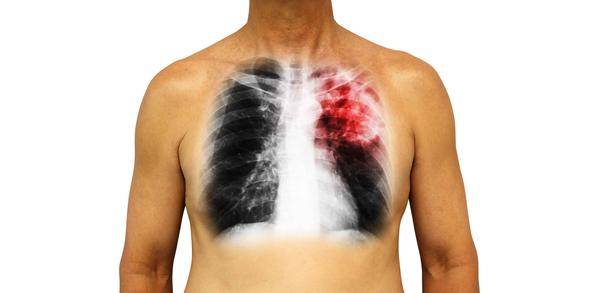

1、感染

癌細胞的生長會大量消耗身體的能量,如此患者自身的免疫能力便會嚴重下降,此外再加上化療會導致白細胞水平降低,在這雙重打擊下,所以肺癌患者會更容易被病菌感染。

肺癌患者的肺部可謂是最容易發生感染的部位,其主要表現為持續性發熱和咳嗽咳痰,且肺部感染也是致使肺癌患者發生死亡的一個主要原因。

所以說,肺癌患者一定要加強對感染的預防,應保證衛生、堅持運動以及合理使用可增強免疫力的藥物。